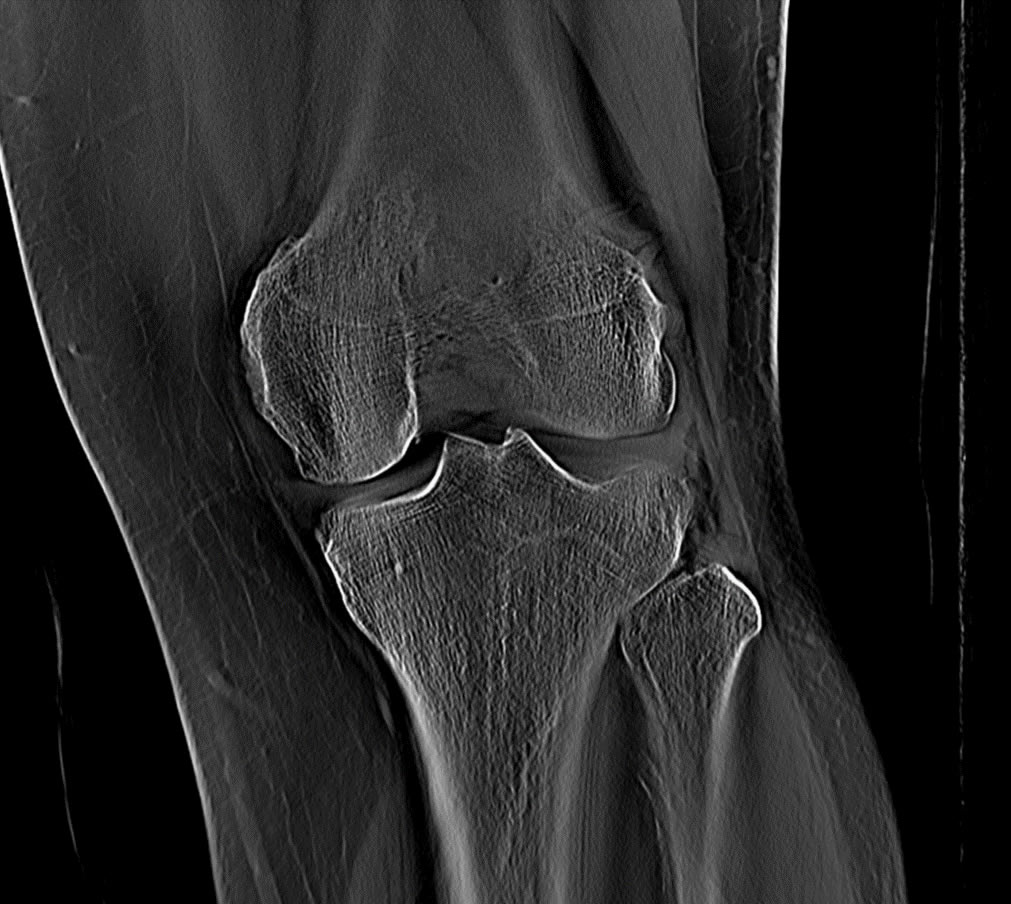

2D Planar radiography

Producing many different imaging modalities

Motion corrected 2D images of morphology